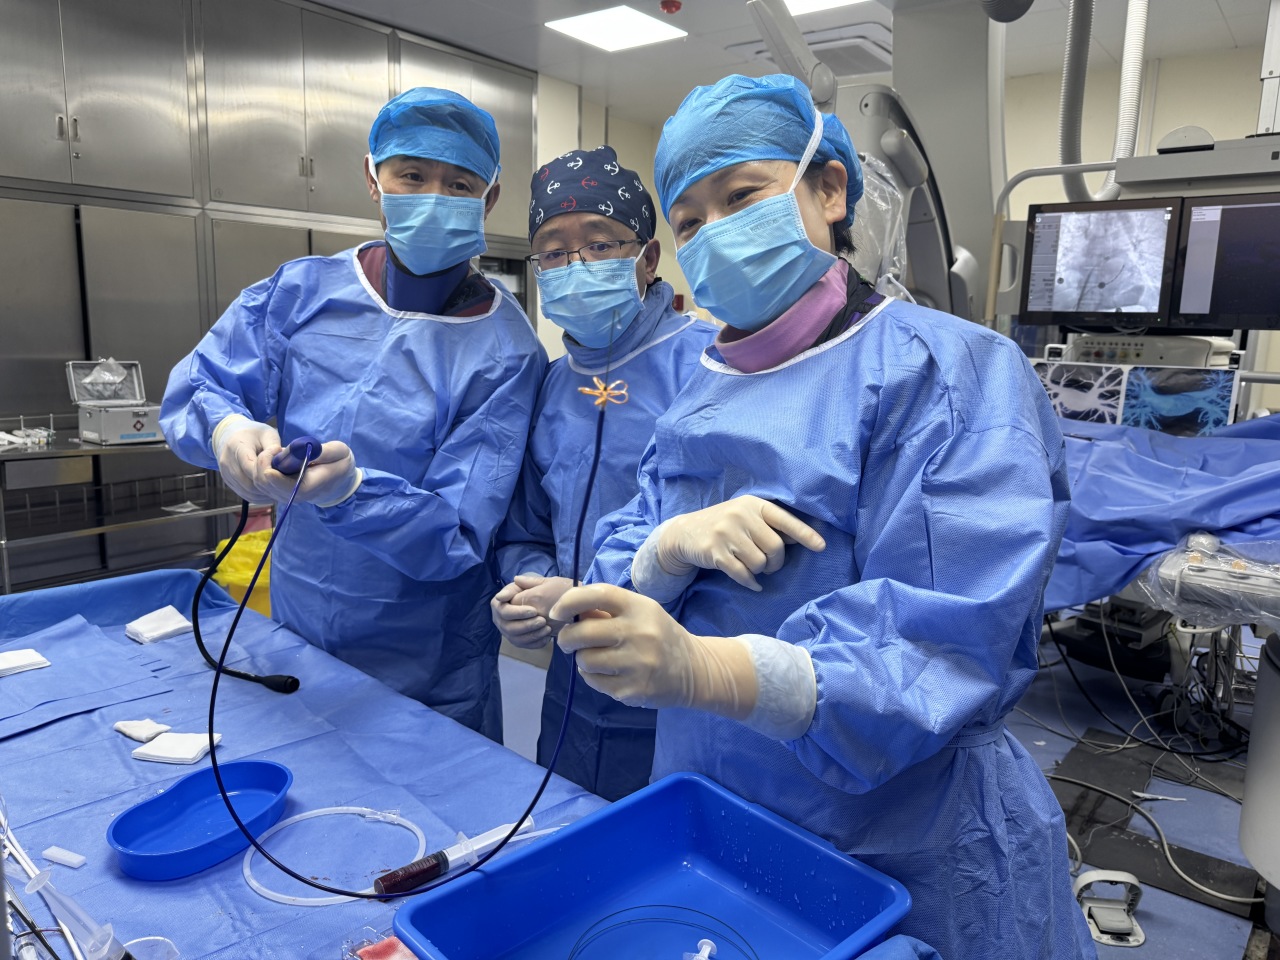

术者风采